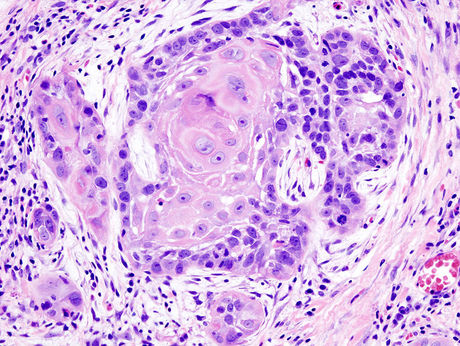

A new study shows how pregnancy hormones can change the epigenome of breast cells, causing cells to become cancerous.

Now a research team from the Walter and Eliza Hall Institute has shown how hormones released during pregnancy can alter the gene expression of breast cells, causing them to become cancerous.

High levels of EZH2 are a marker of poor prognosis in breast cancer and have been frequently observed in basal-like breast cancers, the most aggressive types of breast cancer.